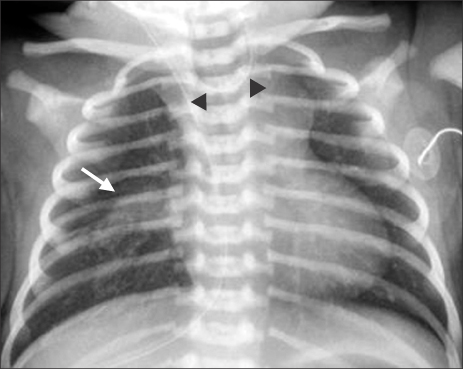

Fig. 1

Infantogram shows coiling of the feeding tube, suggesting esophageal atresia (black arrowheads). Patchy opacity in the right lower lung is observed (white arrow).

Fig. 1 Infantogram shows coiling of the feeding tube, suggesting esophageal atresia (black arrowheads). Patchy opacity in the right lower lung is observed (white arrow).